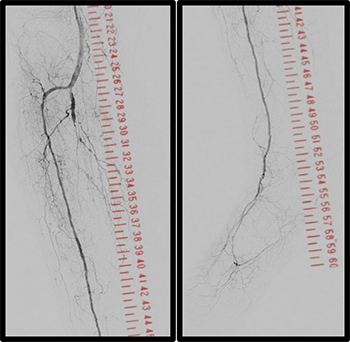

その他、当院で実際に使用した臨床例について示す。(図10、図11、図12)

IGS630_Fukaya_13.jpg図10 IVUSマーキング

IGS630_Fukaya_14.jpg図11 下大静脈フィルター

IGS630_Fukaya_15.jpg図12 VAIVT